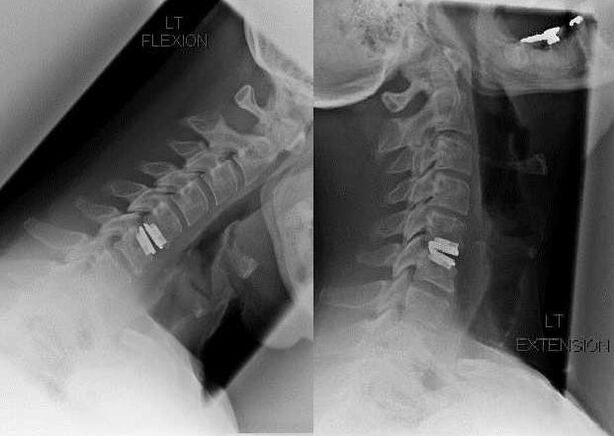

NSAIDs

In the case of radiographic stage 2-3 osteochondrosis, patients complain of sharp, penetrating pain that occurs when tilting or turning the head.In such cases, nonsteroidal anti-inflammatory drugs are prescribed.In case of severe pain, intramuscular injections are used - Diclofenac, Meloxicam, Lornoxicam, Ketorolac.Medicines not only have pain-relieving, but also anti-inflammatory and anti-edema effects.This is especially true if the soft tissues of the neck are damaged by a displaced disc or osteophyte.